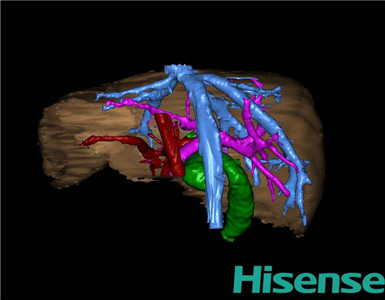

CT结果输入海信CAS系统后行3D重建及手术规划后,于2015-8-18全麻下行“胆总管囊肿切除+胆囊切除+胆总管-空肠吻合术”手术治疗:

将0.625mm双源薄层CT资料的静脉期和动脉期Dicom格式文件导入海信CAS系统。

通过调节窗宽窗位调整CT序号,对肝实质,胆囊,下腔静脉,肿瘤,肝动脉、门静脉及肝静脉等进行三维重建;系统自动计算肝脏体积。

术前三维重建:

重建图片